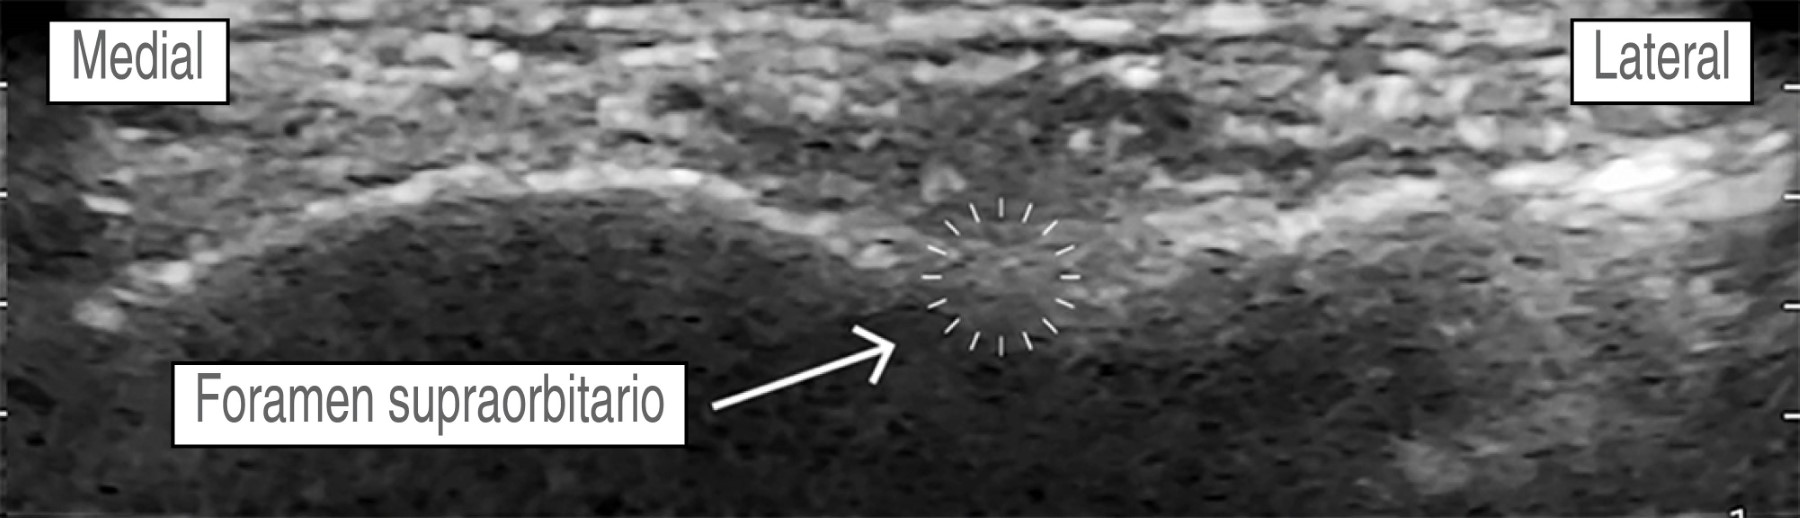

Hombre de 56 años, con diagnóstico de meningioma de la convexidad frontal, con un estado físico de la American Society of Anesthesiologists (ASA) II. Hipertensión arterial esencial en tratamiento regular con losartán 50 mg VO cada 24 horas, sin otros antecedentes. Peso: 87 kg, talla: 1.70 m. Presenta un cuadro clínico de tres meses de evolución caracterizado por cefalea holocraneana, trastornos del comportamiento (apatía, falta de motivación, indiferencia) sin datos de focalización neurológica. La imagen de resonancia magnética muestra una tumoración frontoparietal derecha de 8.2 × 5.1 cm que realza al contraste de forma homogénea, con efecto de masa significativo y desviación de la línea media de 13 mm. Ingresa a sala quirúrgica para craneotomía bifrontal y resección tumoral guiada por neuronavegación. En la sala quirúrgica bajo monitorización invasiva y anestesia total intravenosa con remifentanilo (0.15-0.2 μg/kg/min), propofol (90-120 μg/kg/min), lidocaína (1-2 mg/kg/h) y después de asegurar la vía aérea colocamos un bloqueo de escalpe guiado por USG. Se utilizó una sonda de USG lineal (10 MHz). Nervio supraorbitario y supratroclear: en situación transversal, colocamos la sonda en el hueso frontal sobre el reborde orbitario superior identificando el agujero supraorbitario (muesca). Con técnica en plano, la inyección es superficial al foramen (evitando la administración dentro del foramen), con un volumen de 1.5 mL de anestésico local, para asegurar una cobertura adecuada al nervio supratroclear colocamos otra inyección medial al supraorbitario de 1.5 mL de AL, visualizando su extensión bajo USG. No logramos identificar la arteria supraorbitaria (Figura 2). Nervio cigomático-temporal: colocamos el transductor en un plano coronal, sobre el límite anterior de la fosa temporal, posterior a la apófisis frontal del hueso cigomático, lo que nos deja visualizar tres estructuras: fascia temporal, músculo temporal y hueso temporal, colocamos dos inyecciones de 1.5 mL de AL, en dos puntos de referencia: el hueso temporal (profundo) y la fascia temporal superficial (Figura 3). Nervio auriculotemporal: en el mismo plano facial que el nervio anterior, colocando el transductor en sentido transversal entre el canto lateral del ojo y el trago, identificamos la arteria temporal superficial; el nervio corre en el mismo plano facial que la arteria y lo bloqueamos con 2 mL de AL, evitando la punción vascular (Figura 4). Nervio occipital mayor: colocamos la sonda de USG paralela a una línea que conecta el inión y la mastoides logrando identificar a la arteria occipital junto al nervio. Con inyección en plano utilizamos 2.0 mL de AL (Figura 5). Nervio auricular mayor y occipital menor: bloqueamos ambos nervios a través de un bloqueo de plexo cervical superficial, colocando la sonda transversal sobre la cara lateral del cuello, ubicando el borde posterior del músculo esternocleidomastoideo (ECM) en un punto medio entre la mastoides y la clavícula identificando el plexo como pequeños nódulos hipoecoicos profundos al borde posterior del ECM, el nervio auricular mayor se puede ver comúnmente sobre el músculo ECM. Con técnica en plano la inyección se realizó detrás del ECM, superficial a la fascia prevertebral con un volumen de 5 mL de AL (Figura 6). El bloqueo se realizó de forma bilateral utilizando 28 mL de bupivacaína isobárica a 0.5%, empleando un tiempo de 30 min, se evitó de forma efectiva la respuesta hemodinámica al pinchado, sin necesidad de aumentar la dosis de opioide, o requerir infiltración del área de colocación del pincho, se complementó la analgesia multimodal con paracetamol 1 g IV + ketoprofeno 100 mg IV, no se requirieron rescates de opioide en las 48 horas posteriores y hasta el egreso, se realizó una resección tumoral de 100% sin secuelas neurológicas, no se presentaron complicaciones asociadas al bloqueo de escalpe (punción vascular o déficit nervioso).

Figura 2